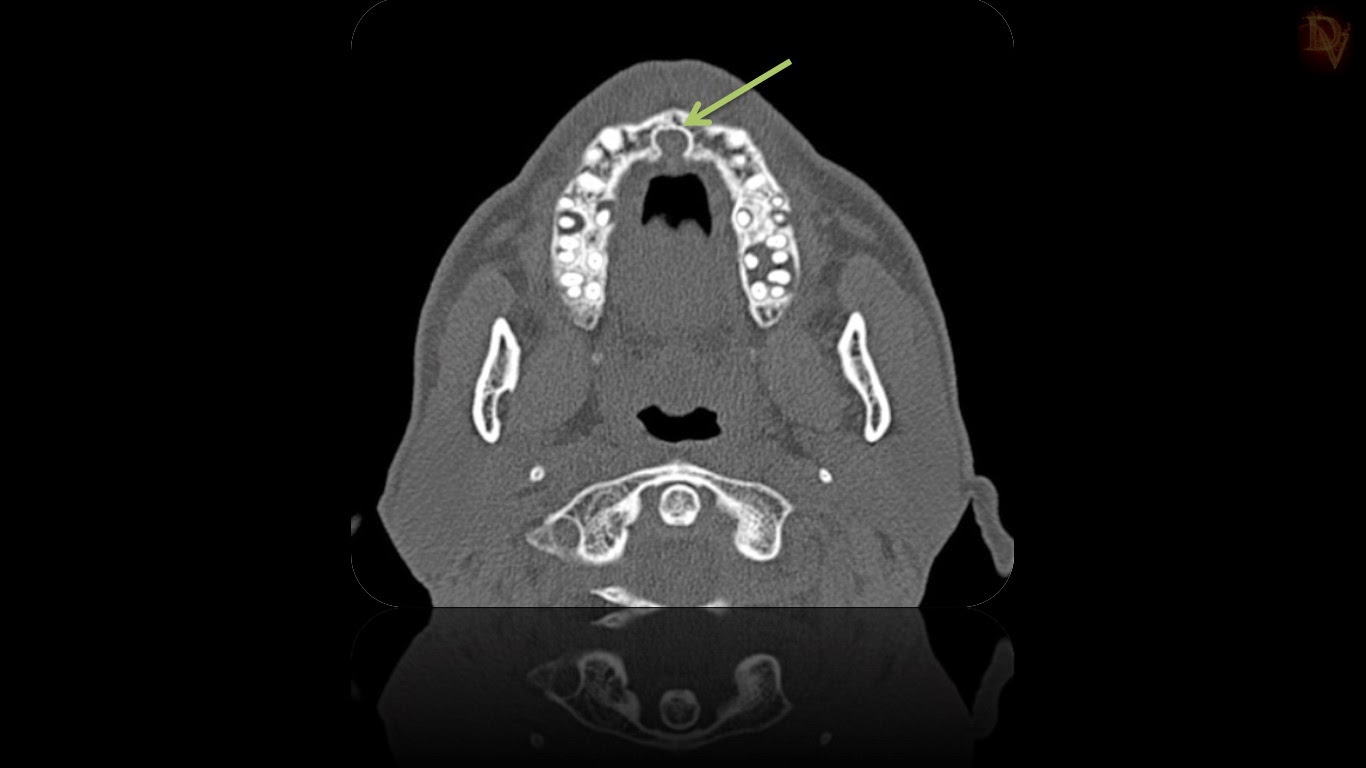

From radiologymri.blogspot.com

Radiology MRI Incisive Canal Incisive Canal Cyst Symptoms It may appear as extrabony incisive papilla cyst or intrabony lesion. Nasopalatine duct cyst, also termed as incisive canal cyst, arises from embryogenic. It appears as either asymptomatic which is recognized on routine. The incisive canal, also known as the nasopalatine canal, is an interosseous. T he nasopalatine duct cyst (npdc), also known as the incisive canal cyst, is the. Incisive Canal Cyst Symptoms.

From radiologymri.blogspot.ca

Radiology MRI Incisive Canal Cyst on CT Incisive Canal Cyst Symptoms The incisive canal, also known as the nasopalatine canal, is an interosseous. They present as swelling of anterior hard palate, sometimes associated with pain and drainage. It may appear as extrabony incisive papilla cyst or intrabony lesion. It appears as either asymptomatic which is recognized on routine. Incisive canal cysts, also known as nasopalatine duct cysts (npdcs), are developmental, nonneoplastic. Incisive Canal Cyst Symptoms.